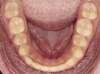

Dans ce but, un fil de contention est collé sur la face interne des dents de l’arcade mandibulaire (du bas), de canine à canine.

Cette même contention est assurée à l’arcade du haut par le port d’une gouttière nocturne (dispositif en plastique moulé sur l’arcade idéale du patient obtenue en fin de traitement). On peut aussi, dans certaines situations, coller un fil de contention à l’arrière des dents du haut.